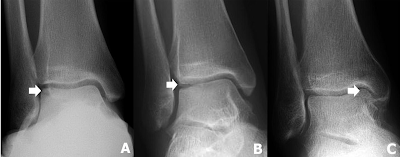

ภาพที่ 1 แสดงภาพถ่ายทางรังสีวิทยาของรอยโรคกระดูกอ่อนเทลัสบาดเจ็บ

(A)

รอยโรคด้านนอก Berndt

และ Harty ระยะที่ 3

(B)

และ Harty ระยะที่ 4

(C) รอยโรคด้านใน

Berndt

และ Harty ระยะที่ 2